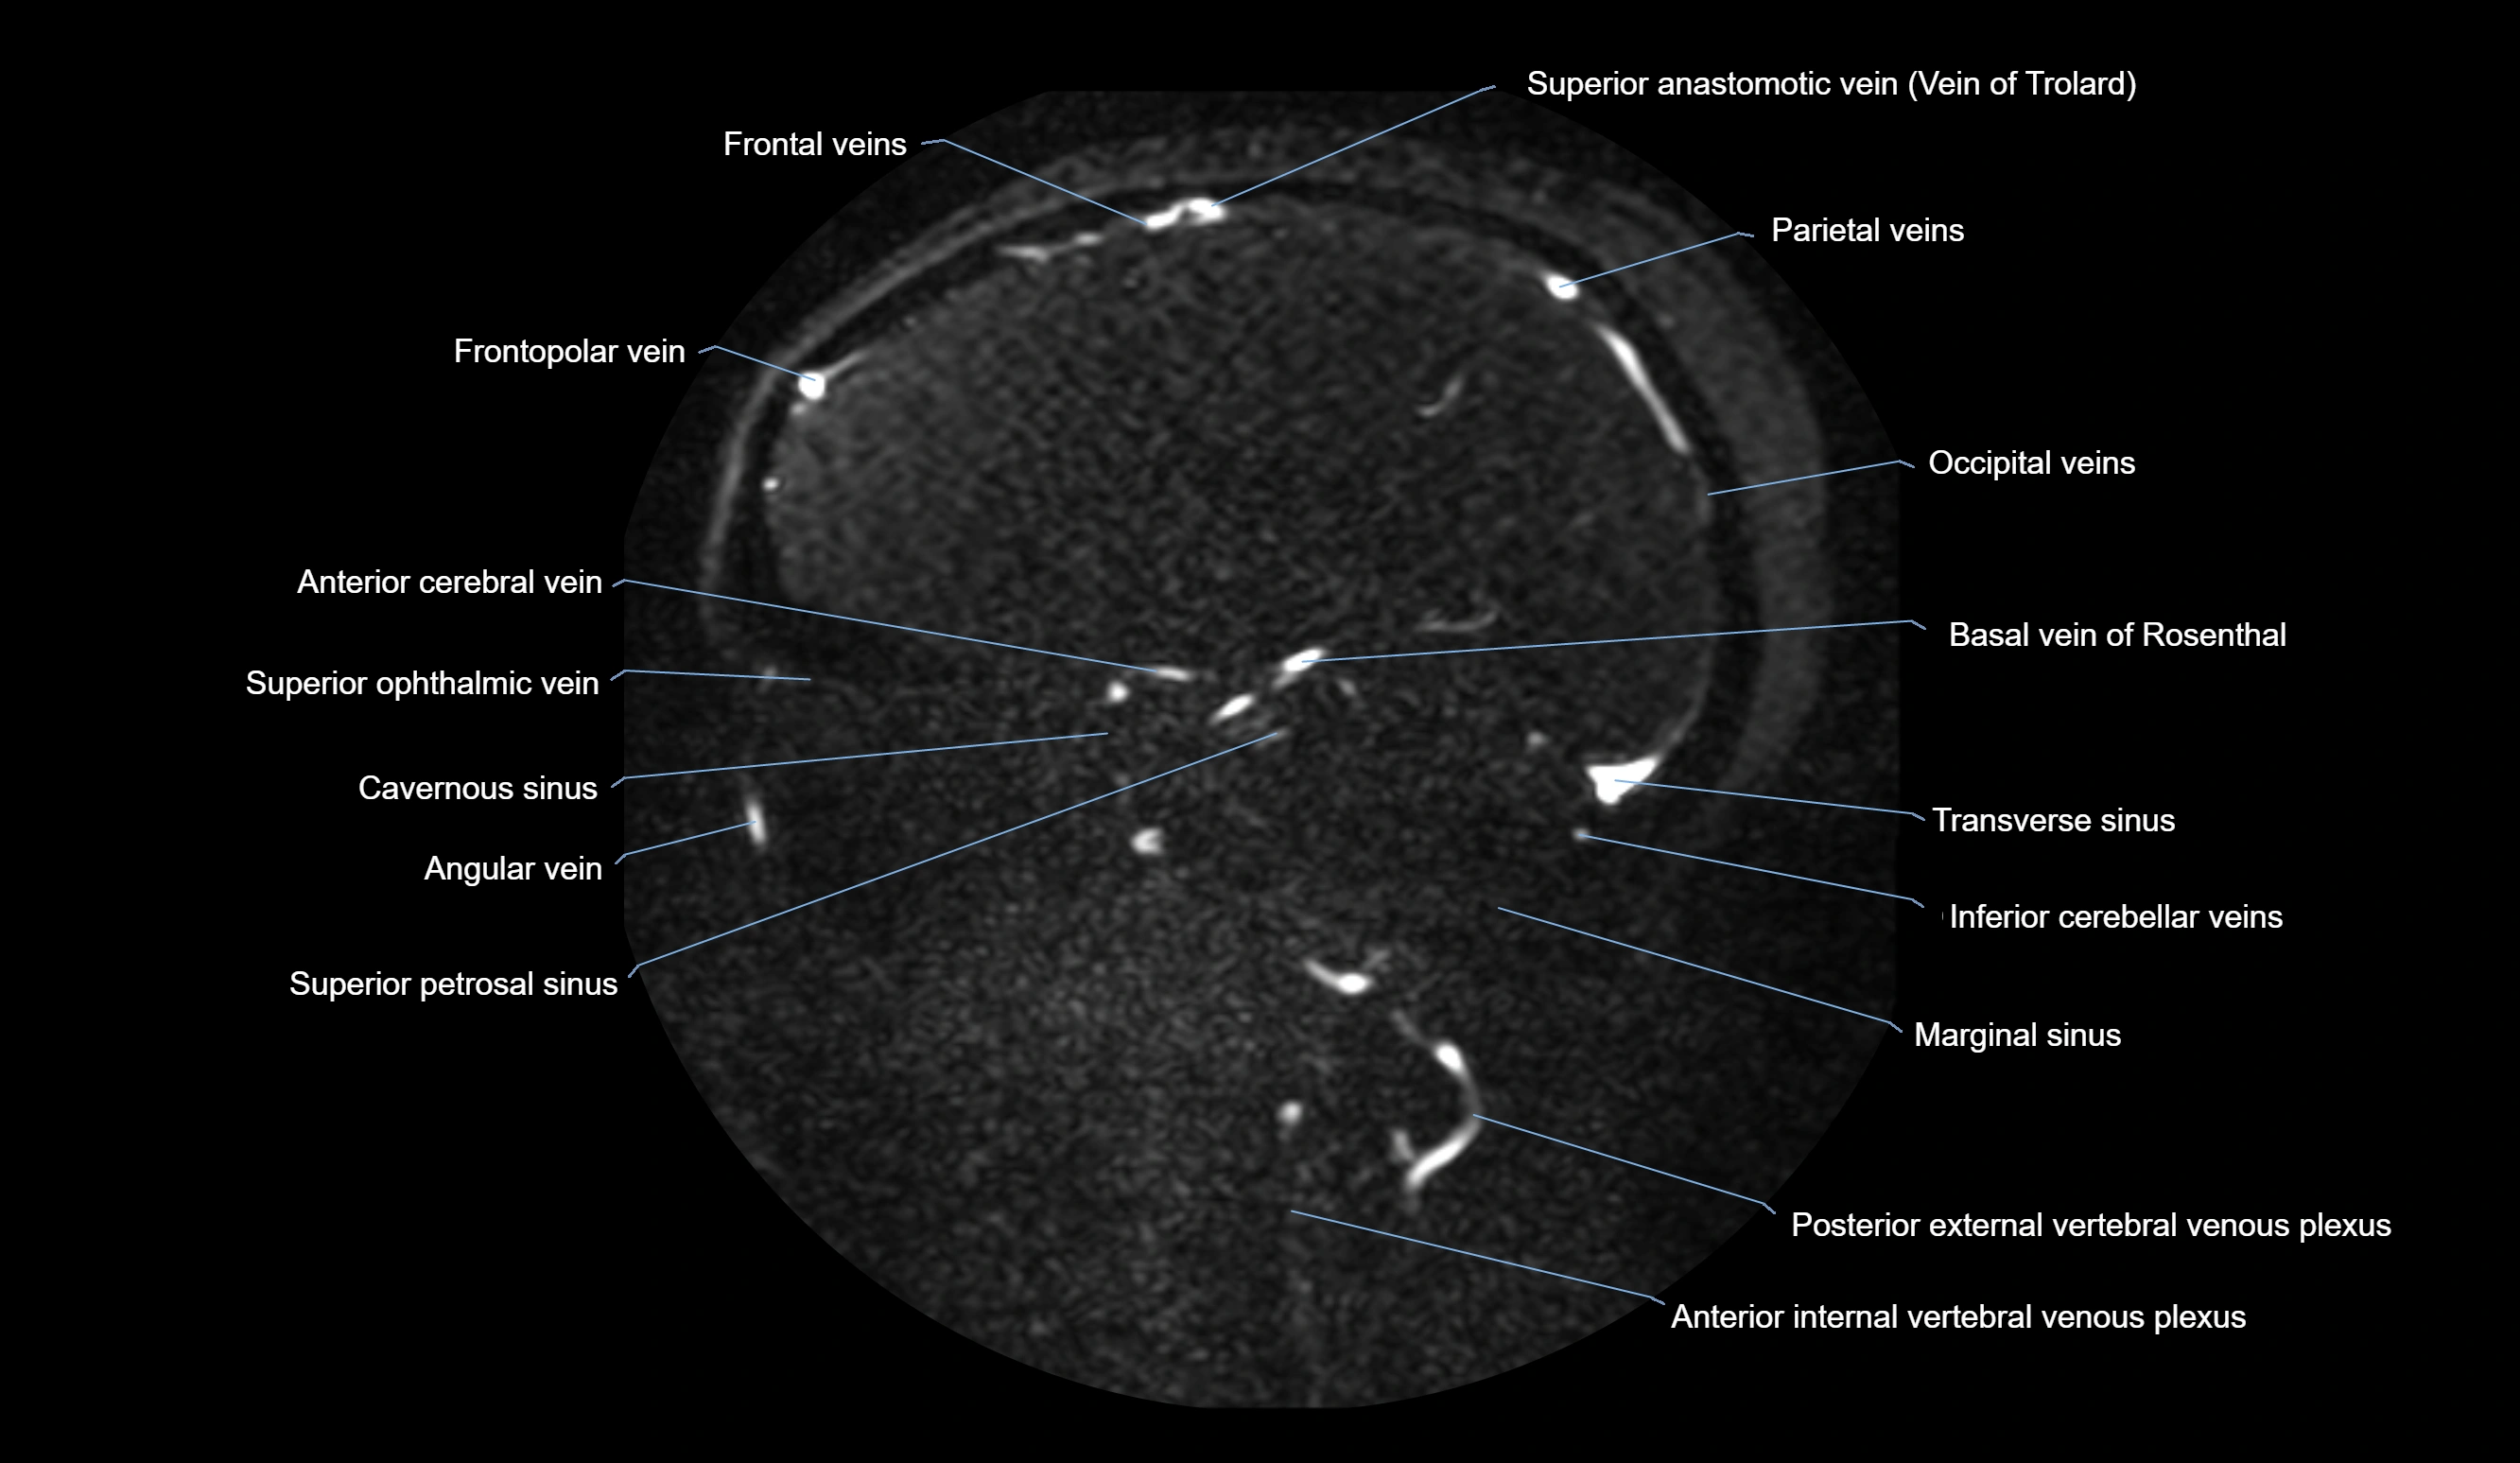

MRI images

image